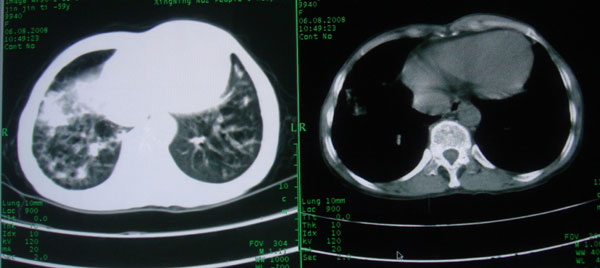

慢性支气管炎伴全小叶型肺气肿、支气管扩张、感染、间质纤维化